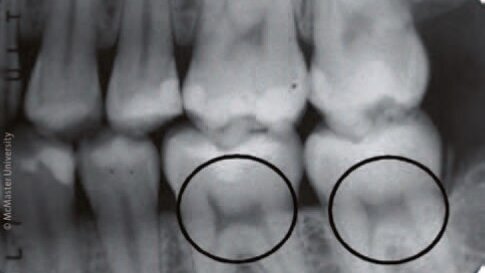

Da bi se izognili tratenju dragocenih vzorcev, so raziskovalci iskali način, s katerim bi izolirali zobe za nadaljnje raziskovanje. S proučevanjem oblik pulpnih rogov na RTG posnetkih so raziskovalci opazili konsistenten, prepoznaven vzorec, ki bi jim lahko pomagal pri raziskovanju arheoloških zob kot tudi pri ugotavljanju pomanjkanja vitamina D pri današnjih pacientih.

Oblika pulpe pri zobeh zdrave osebe spominja na lok, na vrhu katerega sta mačji ušesi; pri osebi s hudim pomanjkanjem vitamina D pa je ta lok asimetričen in zožen, običajno je videti kot profi l stola z naslonjalom.

Tudi predhodne raziskave D'Ortenzove in Brickleyeve so potrdile tovrsten prepoznaven vzorec in njuno proučevanje tako historičnih kot sodobnih zob je potrdilo, da so rentgenski posnetki konsistenten in zanesljiv indikator preteklega pomanjkanja vitamina D.